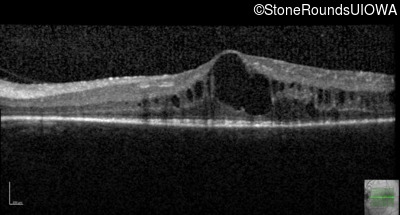

Optical Coherence Tomography - Right - 20/30 -2

Exemplar / OCT Stack

OCT Stack